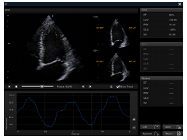

AUTO EF

La evaluación de la función cardíaca requiere precisión y velocidad, ya que se deben realizar varios cálculos. Auto EF, basado en la tecnología de seguimiento de moteado, adquiere EF 2D y volúmenes dentro de un flujo de trabajo optimizado.